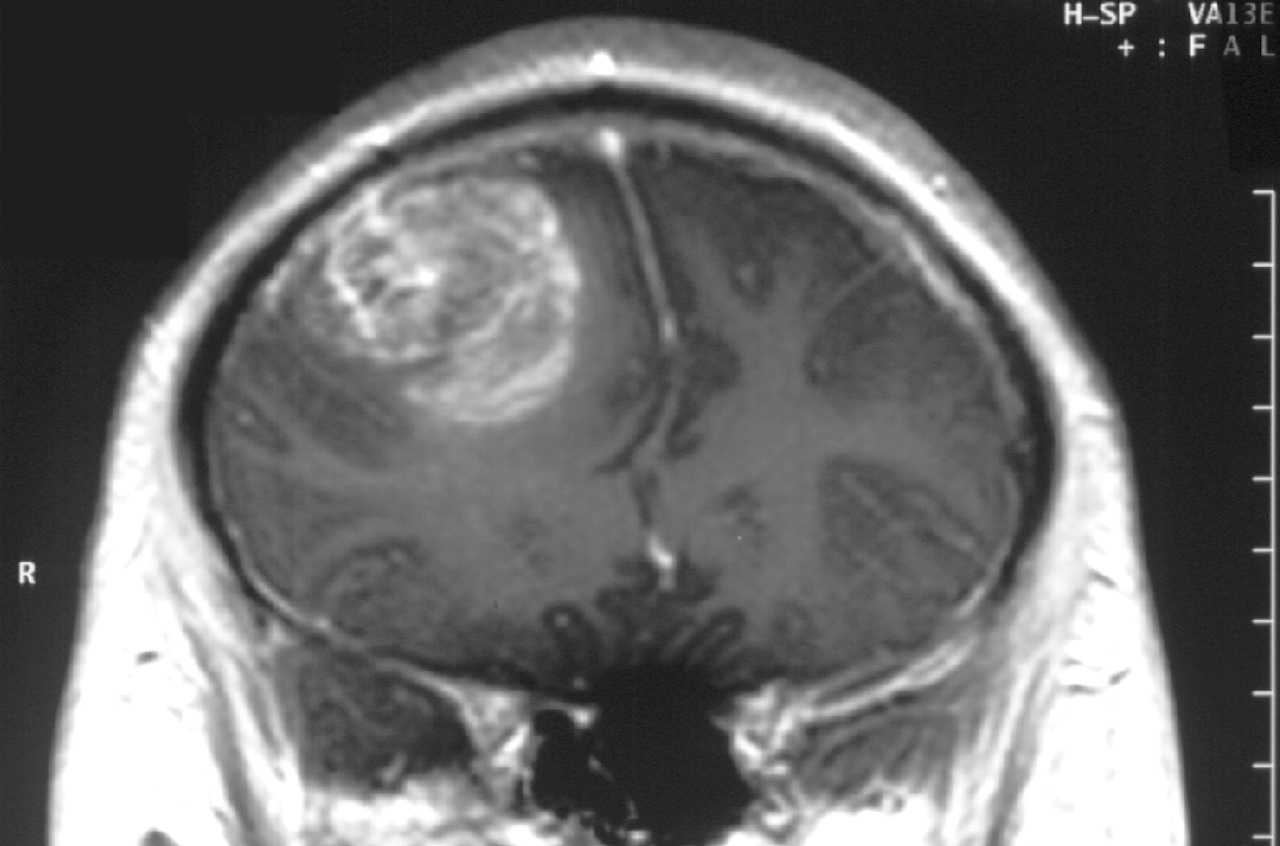

Гліобластома належить до найагресивніших форм раку: після діагнозу пацієнти живуть у середньому трохи більше як рік, а пухлина майже завжди повертається навіть після комплексного лікування. Повторні пухлини відрізняються особливою стійкістю до терапії, і саме це робить хворобу практично невиліковною. Одним із можливих пояснень є пластичність клітин — їхня здатність змінювати стан і форму, що дозволяє раку уникати дії ліків. Проте, що саме запускає таку пластичність, залишалося невідомим.

Науковці припускали, що початкове лікування хімієтерапією чи опроміненням може руйнувати скупчення ракових клітин, звані кластерами, і сприяти їхньому розсіюванню, залишаючи після себе більш пластичні та агресивні клітини. Команда з Комплексного онкологічного центру Сильвестера Університету Маямі вирішила перевірити цю гіпотезу, використовуючи різні моделі пухлин.